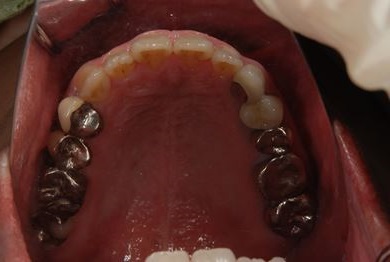

| 性別/年齢 | 女性 / 46歳 | ||||||||||||||||||||||||||||||||

| 主訴 | 歯ぐきがただれてる。歯が少しうずく。 | ||||||||||||||||||||||||||||||||

| 治療方針 | インプラント治療にて、機能的・審美的回復を行う。 | ||||||||||||||||||||||||||||||||

| 治療内容 | インプラント1本(GBR)、ハイブリッドセラミック1本 | ||||||||||||||||||||||||||||||||